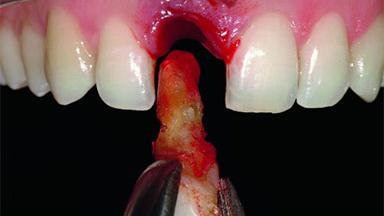

Replacement of an Upper Right Central Incisor with Root Resorption: Ridge Preservation, Delayed Placement of an NC Bone Level Roxolid Implant

A 32-year-old female Caucasian patient with a compromised maxillary right central incisor was referred to us by a general dentist. Her chief complaints were discomfort and mobility of tooth 11 with unsatisfactory esthetics due to discoloration. The patient reported a previous trauma, some years earlier, as the origin of pathology on the afflicted tooth. Anamnesis was negative for any other dental or periodontal pathology in the remaining dentition. The patient did not take any medication and reported to be a light smoker (5–10 cigs/day). She had high esthetic expectations of her treatment. The extraoral examination revealed a high smile line with full exposure of her maxillary teeth and surrounding soft tissue in the area between the second premolars.